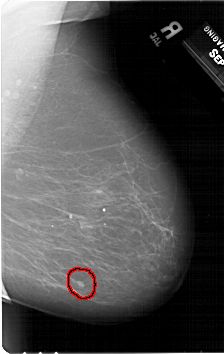

A_1354_1.RIGHT_CC

RIGHT_CC LINES 6871 PIXELS_PER_LINE 4456 BITS_PER_PIXEL 12 RESOLUTION 43.5 OVERLAY

FILE: A_1354_1.RIGHT_CC.OVERLAY

TOTAL_ABNORMALITIES 1

ABNORMALITY 1

LESION_TYPE MASS SHAPE OVAL MARGINS CIRCUMSCRIBED

ASSESSMENT 4

SUBTLETY 3

PATHOLOGY BENIGN

TOTAL_OUTLINES 1

BOUNDARY